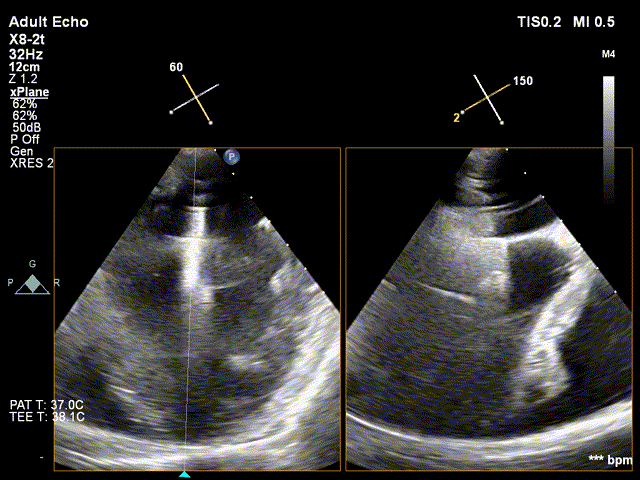

全麻后,首先在心前区的肋间切开3-4CM小切口,暴露心脏的心尖位置,心尖穿刺后进入导丝,利用导丝交换导管鞘完成通路建立。将系统送入左心房,顺利到达二尖瓣病变区域。在经食道超声引导下,术者通过反复评估二尖瓣反流位置、抓捕位置、反流程度,在2区主动脉瓣与二尖瓣闭合线垂直进行巧妙夹合,最终植入一枚ValveClamp®MVC-Ⅲf夹。超声评估夹子固定良好,组织桥完整,无葫芦征,位置、轴向均符合预期。患者术后反流程度从大量转至少量,手术取得圆满成功。患者恢复良好,已经顺利出院。

反流得到明显改善 术后3D动图

术后平均跨瓣压差3mmHg